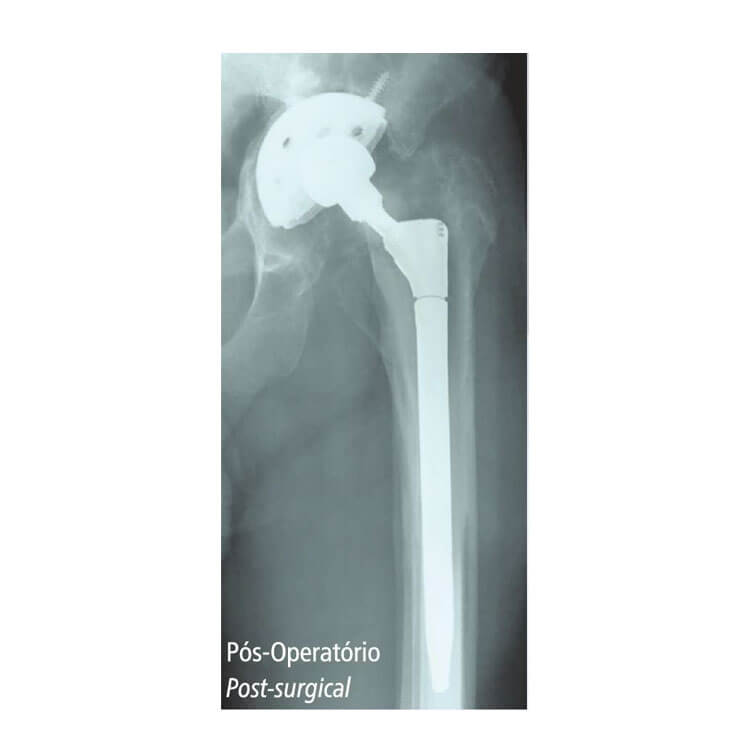

Sistema de Prótese Modular para Revisão de Quadril

Sistema Modular – por se tratar de uma cirurgia com diferentes níveis de complexidade, este sistema é flexível, atendendo a diversas situações nas quais o cirurgião pode se deparar; após a implantação do componente intra-medular, é possível modificar a rotação do componente metafisiário, obtendo-se uma anteversão adequada.